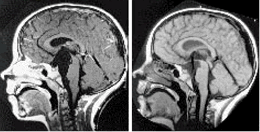

蛛網膜囊腫術前(左)術後(右)對比蛛網膜囊腫患者的最佳治療方案仍有許多爭論。有觀點認為當患者無顱內高壓症狀或無神經系統定位損害時應保守治療,因為有部分患者在行手術探察或切除術後出現不能預知的惡化或死亡。主要是囊腫過份急速減壓使腦組織移位或出現術後感染、出血等嚴重併發症。也有觀點認為即使無症狀患者手術治療可以減少微小損傷導致硬膜下血腫的機率,兒童在無症狀時手術治療可以解除腦葉發育不全,腦組織代謝異常等囊腫對腦功能潛在的影響。當囊腫不斷增大引起顱壓增高或與之相關的腦積水、硬膜下血腫、神經定位損害、與囊腫相關癲癇發作,影像學提示腦組織壓迫時應考慮手術治療。手術治療的目的是解除壓迫。